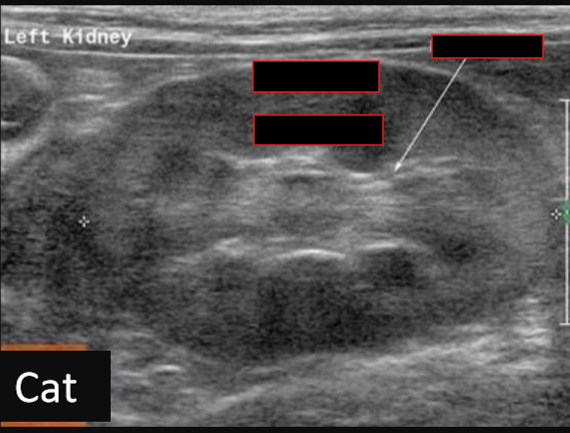

Label this frontal/dorsal kidney ultrasound

A

Label this frontal/dorsal view kidney ultrasound